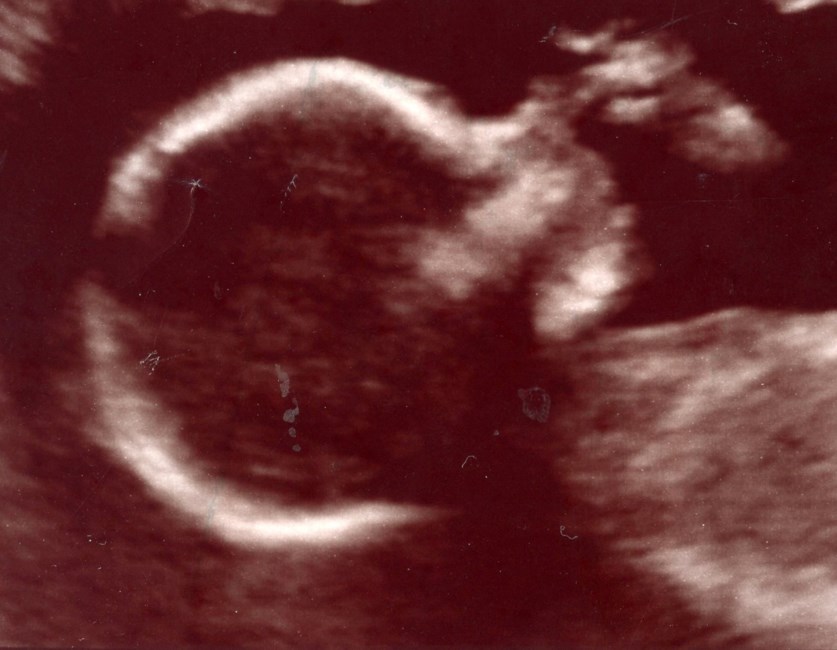

Emry Belle Borunda of Midland, Texas passed away in her mother’s womb. Her heart stopped beating at 20 weeks. She was born into Heaven in God’s hands. Emry was delivered on August 8 of 2016. Even with the little precious time we had with Emry, she brought nothing but an abundance of love, warmth to our hearts and bitter-sweet tears. But through it all, God’s presence was with us as well as Emry’s. She left footprints in our hearts and touched many lives. Heaven’s gain was our loss.